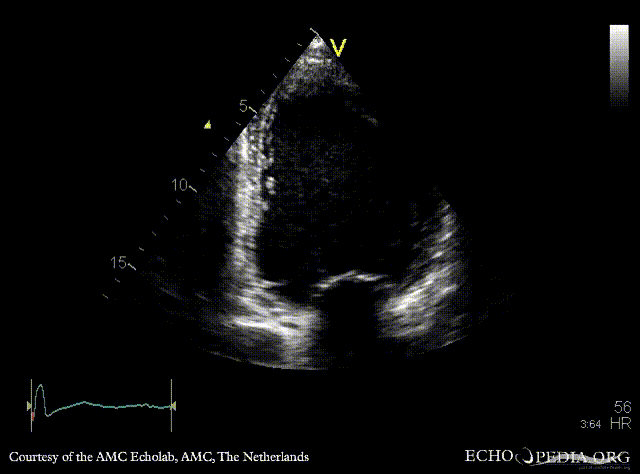

| A2CH | A3CH |